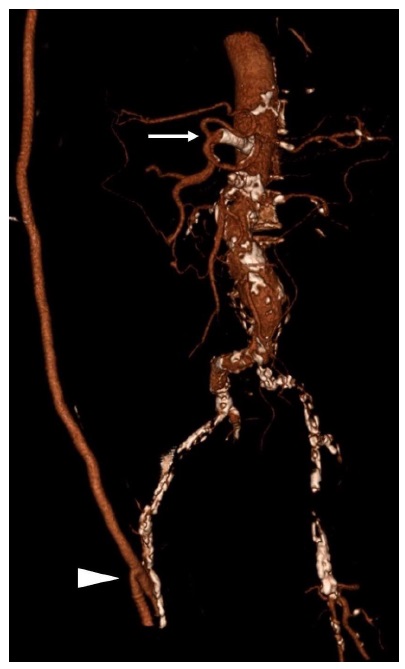

He was readmitted to the hospital 32 days after the discharge with abdominal pain, vomits, and constipation. Physical examination revealed abdominal pain and tenderness to palpation. CT scan showed ileum adhesion to a thickened cecum; the celiac trunk had a severe degree of stenosis, and the SMA was occluded. Analytically presented leukocytosis and an elevated c-reactive protein. He initiated antibiotic therapy (piperacillin + tazobactam) and parenteral nutrition. Seven days later, he was submitted to a celiac trunk primary stenting with a balloon-expandable stent (figures 3 and 4). Five days after the vascular procedure he was submitted to a right colectomy with segmental enterectomy by colorectal surgeons (figure 5). The postoperative period was uneventful, and he was discharged on the ninth day after the surgical procedure. At a 6-month follow-up, the patient remains without any gastrointestinal symptoms.

The procedure was made in the emergency room by an open approach in the female patient: superior mesenteric artery (SMA) thrombectomy and retrograde stent placement at the occlusion site. The procedure was only partially effective, and four months later, she presented SMA thrombosis at the stent level. Maybe the presence of the JAK2 V617F mutation contributed to the new thrombotic event11. In this phase, the solution to the problem was made with an open ileohepatic bypass. A resolution of ischemic ileal stenosis occurs without the need for enterectomy. This way, it was possible to avoid another intestinal surgery and the risk of short bowel syndrome. In the man patient submitted to a right axillofemoral bypass with a sequential popliteal bypass already with CMI and the need for gastrointestinal revascularization before colorectal surgery; the option was the celiac trunk primary stenting. This solution allowed a safe and effective elective colorectal intervention.